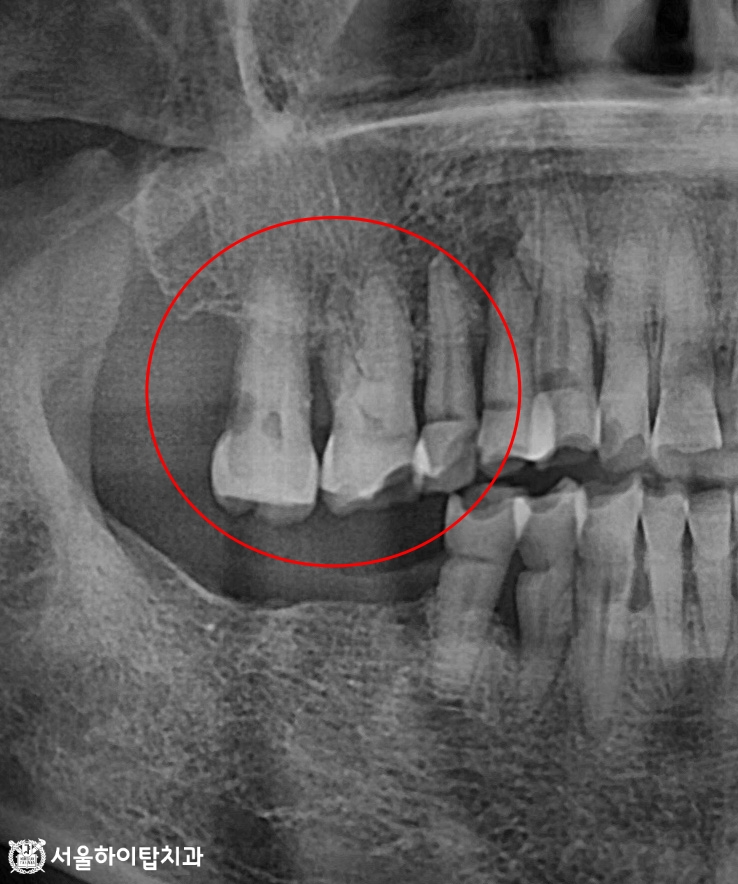

이에 따라 파노라마 엑스레이를 보면

저작이 이루어지는 치아 뿌리 끝에서

방사선 투과상으로 염증성 병소가 관찰됩니다.

여기에 더해, 전반적으로 치조골이 흡수되어

뼈의 높이가 낮아진 상태 또한 확인됩니다.

즉, 동암역 치과 에서는 저작 불균형으로 특정 치아에 과도한 힘이 집중되면서,

단순한 마모를 넘어 치조골 손상과 염증까지 발생한 것으로 볼 수 있습니다.